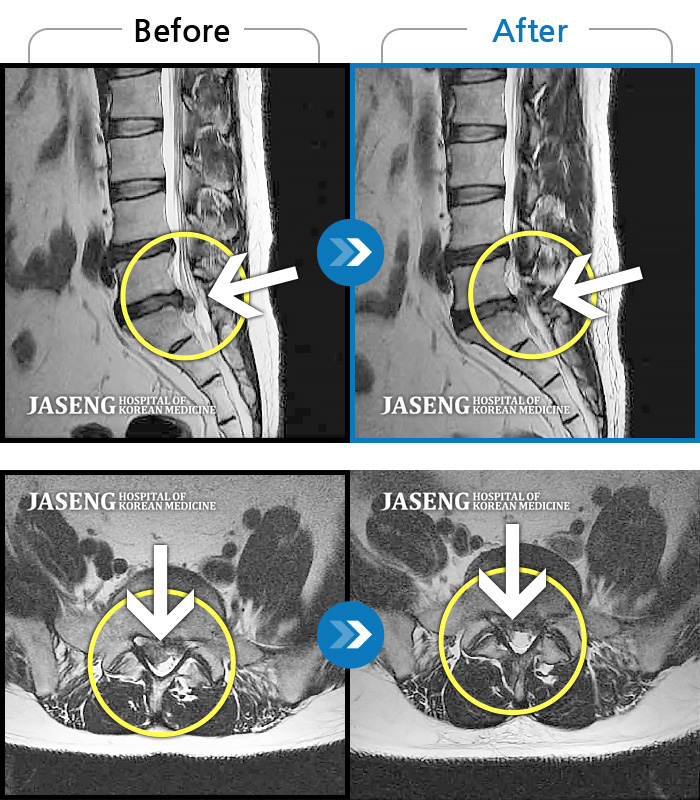

[뱸] 19.11.28~25.05.06

ȯںп Ǹ ǿ ԿǾ, ο ġ ۿ Ƿ ġḦ Ͻñ ٶϴ.